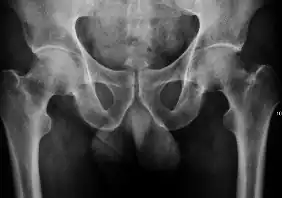

Projectional radiography ("X-ray") is the first imaging technique of choice in hip pain, not only in older people with suspected osteoarthritis but also in young people without any such suspicion. In this case plain radiography allows categorization as normal hip or dysplastic hip, or with impingement signs, pincer, cam, or a combination of both.[1]

Projectional radiography ("X-ray") is currently useful not only in older people in whom osteoarthritis of the hip is suspected but also in younger people without osteoarthritis, who are being evaluated for femoroacetabular impingement (FAI) or hip dysplasia.[1]

Plain radiography allows us to categorize the hip as normal or dysplastic or with impingement signs (pincer, cam, or a combination of both). Besides these, pathologic processes like osteoarthritis, inflammatory diseases, infection, or tumors can also be identified (Figure 1).[1]

- Hip dysplasia

Measurements of hip dysplasia in adults are quite different from those in children.[1]

- Osteoarthritis

In adults, one of the main indications for radiographs is the detection of osteoarthritic changes (Figure 1(e)). Nevertheless, radiographs usually detect advanced osteoarthritis that can be graded according to the Tönnis classifications. The grading system ranges from 0 to 3, where 0 shows no sign of osteoarthritis. Intermediate grade 1 shows mild sclerosis of the head and acetabulum, slight joint space narrowing, and marginal osteophyte lipping. Grade 2 presents with small cysts in the femoral head or acetabulum, moderate joint space narrowing, and moderate loss of sphericity of the femoral head. Grade 3 is the severest form of osteoarthritis, which manifests as severe narrowing of the joint space, large subchondral cyst with productive bone changes that may lead to deformity of the bone components of the joint, while secondary osteoarthritis due to calcium pyrophosphate deposition can be diagnosed when calcification of hyaline cartilage and fibrocartilage is detected.[1]